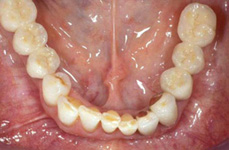

Náhrada jednoho zubu

Náhrada jednoho zubu pomocí implantátu je možná také v postranním úseku chrupu. Při ztrátě většího počtu zubů ve frontálním nebo postranním úseku může být mezer uzavřena větším počtem jednotlivých implantátů.

Při ošetření pomocí jednotlivých implantátů zůstávají sousední zuby neporušené – intaktní. Při klasickém ošetření pomocí můstků musejí být tyto zuby obroušeny!